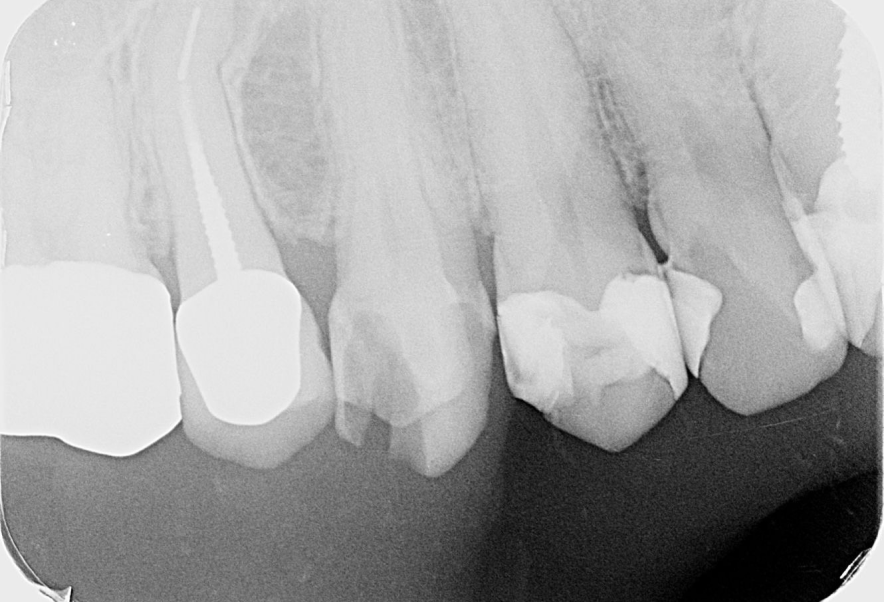

Before

After

他院で抜歯と診断された歯の精密根管治療